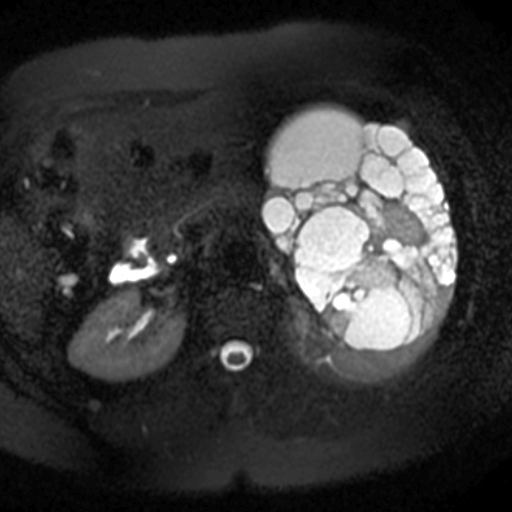

Adult Polycystic Kidney Disease (Apkd) ( Fig. 4.5 )

What are the 6 associations of this condition?